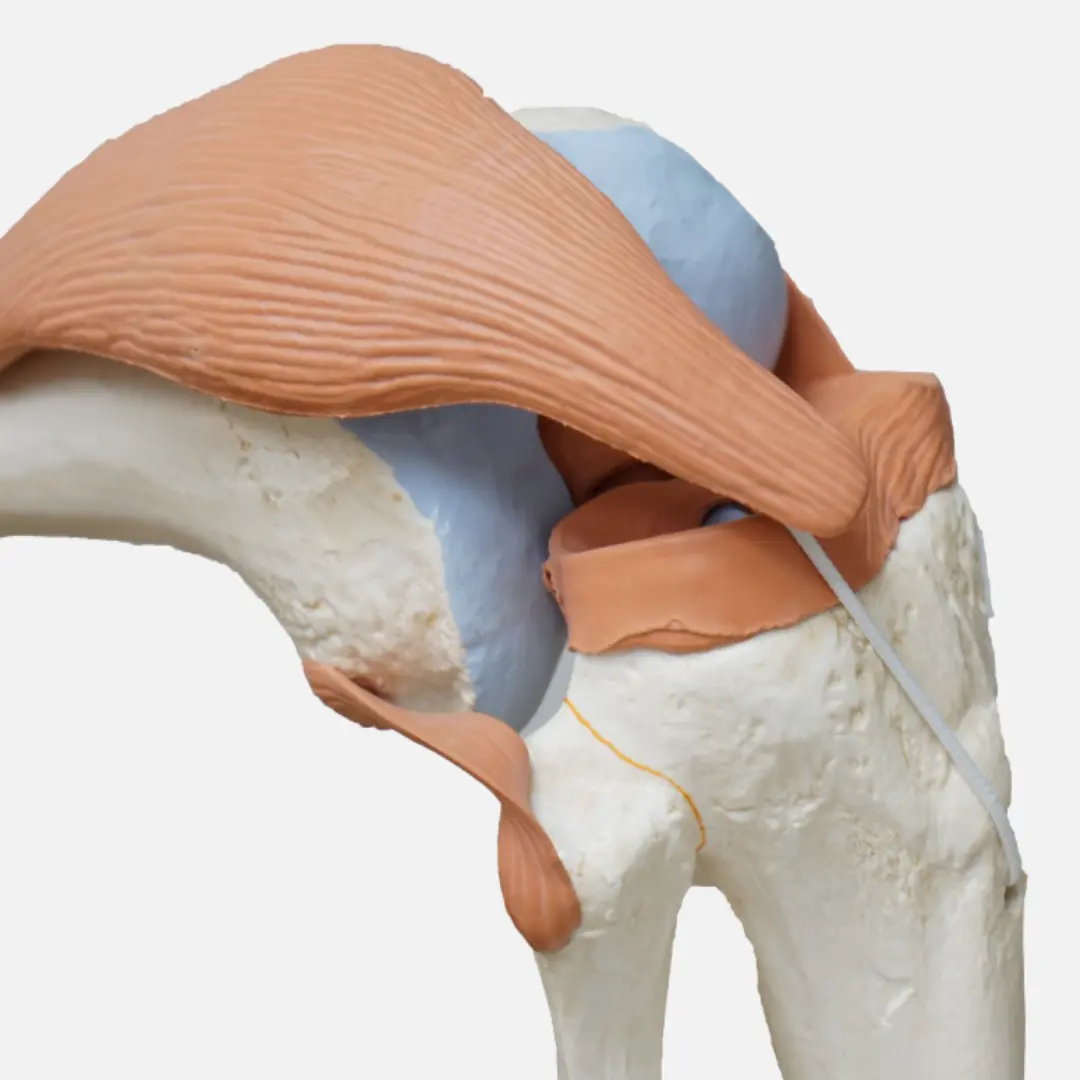

관절 건강에 대한 관심이 높아지면서 콘드로이친이 주목받고 있어요. 콘드로이친은 관절 연골의 주요 구성 성분으로, 관절 건강 유지에 필수적인 역할을 하죠. 콘드로이친 효능부터 건강하게 콘드로이친 복용하는 방법까지 정리해볼게요!

콘드로이친은 다양한 효능을 통해 관절 건강을 지켜줘요.

- 관절 통증 완화:

- 관절 염증을 줄여 통증 완화에 도움을 줘요.

- 관절의 움직임을 부드럽게 하여 활동성을 높여줍니다.

- 골관절염 개선:

- 골관절염 진행 속도를 늦추고 증상 완화에 효과적인 도움을 줄 수 있어요.

- 관절의 기능을 개선하여 일상생활의 불편함을 줄여줍니다.